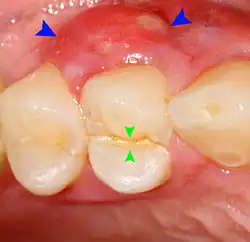

Clinical & xray correlation of pericoronitis

clinical shot of pericoronitis

An operculum (green arrow) over a partially erupted lower left third molar tooth. There is minimal inflammation and recurrent swelling.

xray of pericoronitis

A radiograph of the above tooth showing chronic pericoronitis, operculum (blue arrow) and bone destruction (red arrow) from chronic inflammation. Tooth is slightly disto-angular.

Pericoronitis is inflammation of the soft tissues surrounding the crown of a partially erupted tooth.[25] The lower wisdom tooth is the last tooth to erupt into the mouth, and is, therefore, more frequently impacted, or stuck, against the other teeth. This leaves the tooth partially erupted into the mouth, and there frequently is a flap of gum (an operculum), overlying the tooth. Bacteria and food debris accumulate beneath the operculum, which is an area that is difficult to keep clean because it is hidden and far back in the mouth. The opposing upper wisdom tooth also tends to have sharp cusps and over-erupt because it has no opposing tooth to bite into, and instead traumatizes the operculum further. Periodontitis and dental caries may develop on either the third or second molars, and chronic inflammation develops in the soft tissues. Chronic pericoronitis may not cause any pain, but an acute pericoronitis episode is often associated with pericoronal abscess formation. Typical signs and symptoms of a pericoronal abscess include severe, throbbing pain, which may radiate to adjacent areas in the head and neck,[21][26]: 122  redness, swelling and tenderness of the gum over the tooth.[27]: 220–222  There may be trismus (difficulty opening the mouth),[27]: 220–222  facial swelling, and rubor (flushing) of the cheek that overlies the angle of the jaw.[21][26]: 122  Persons typically develop pericoronitis in their late teens and early 20s,[28]: 6  as this is the age that the wisdom teeth are erupting. Treatment for acute conditions includes cleaning the area under the operculum with an antiseptic solution, painkillers, and antibiotics if indicated. After the acute episode has been controlled, the definitive treatment is usually by tooth extraction or, less commonly, the soft tissue is removed (operculectomy). If the tooth is kept, good oral hygiene is required to keep the area free of debris to prevent recurrence of the infection.[21]: 440–441